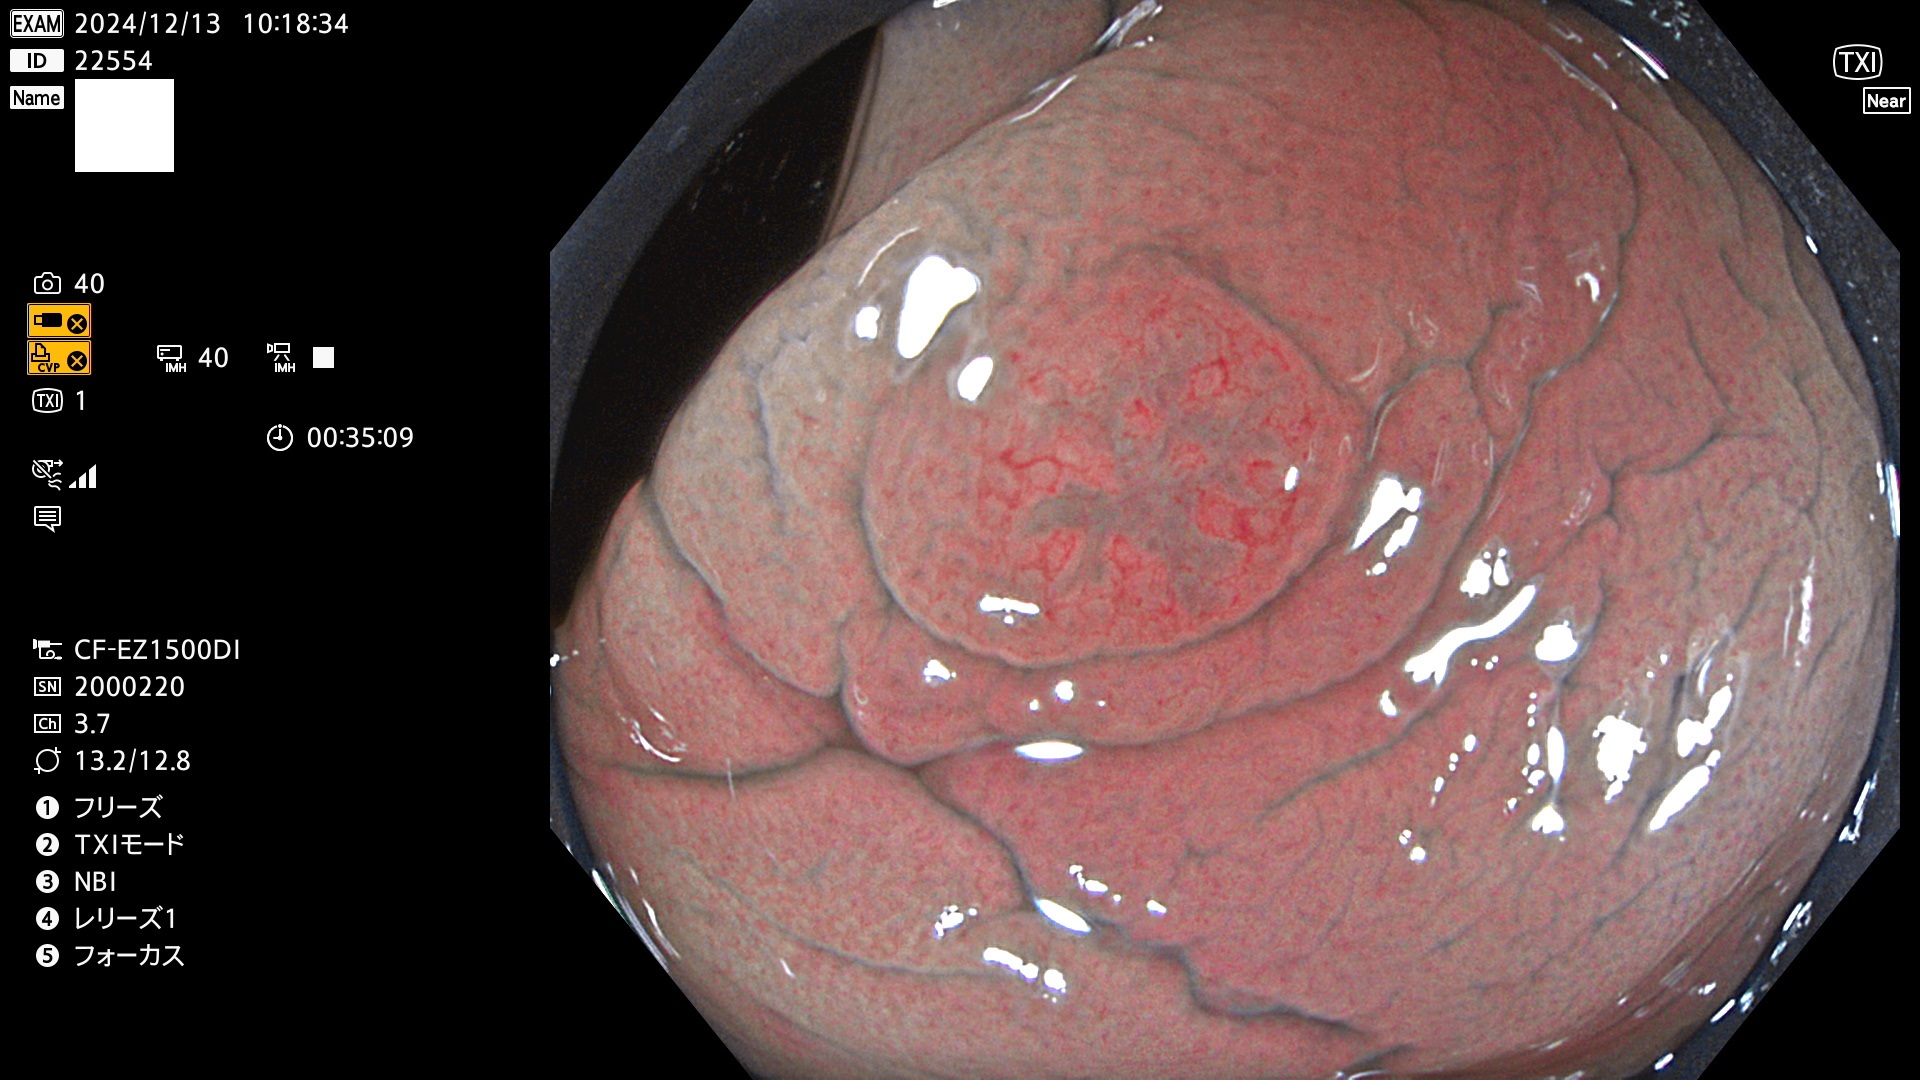

今週のUb、Uc型腺腫

完全に平坦な物をUb、陥凹している物をUcと呼びます。最も発見が難しく危険な病変です。

毎週の検査(木・金・土・日)に発見されたUb、Uc型・腺腫を、その週の日曜の夜にUPし1週間、提示します。

抽出の対象期間 2024年12月12日〜12月16日の5日間(60件の検査)13件 (13/60=21%)